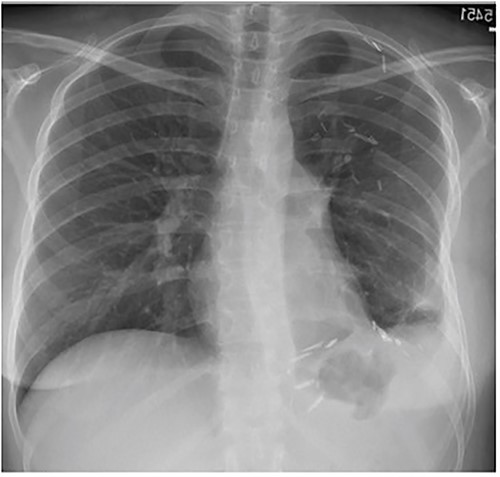

A 33-year-old woman presented to the emergency department following a motor vehicle accident. Imaging showed a large heterogenous intermediate density mass filling and expanding the left hemithorax, causing a complete collapse of the left lung and substantial right deviation of heart and mediastinum (Fig. 1). The patient complained of mild exertional dyspnea that had worsen over the past 6 months. Physical exam was unremarkable aside from decreased breath sounds on left side. Percutaneous core needle biopsy revealed spindle cells along with immunostatins consistent with SFT. Upon later questioning, the patient noted progressive anorexia with a 15 lb weight loss over the last 4 months and occasional dyspnea.

Frontal chest radiograph shows complete opacification of left hemithorax with significant mass effect.